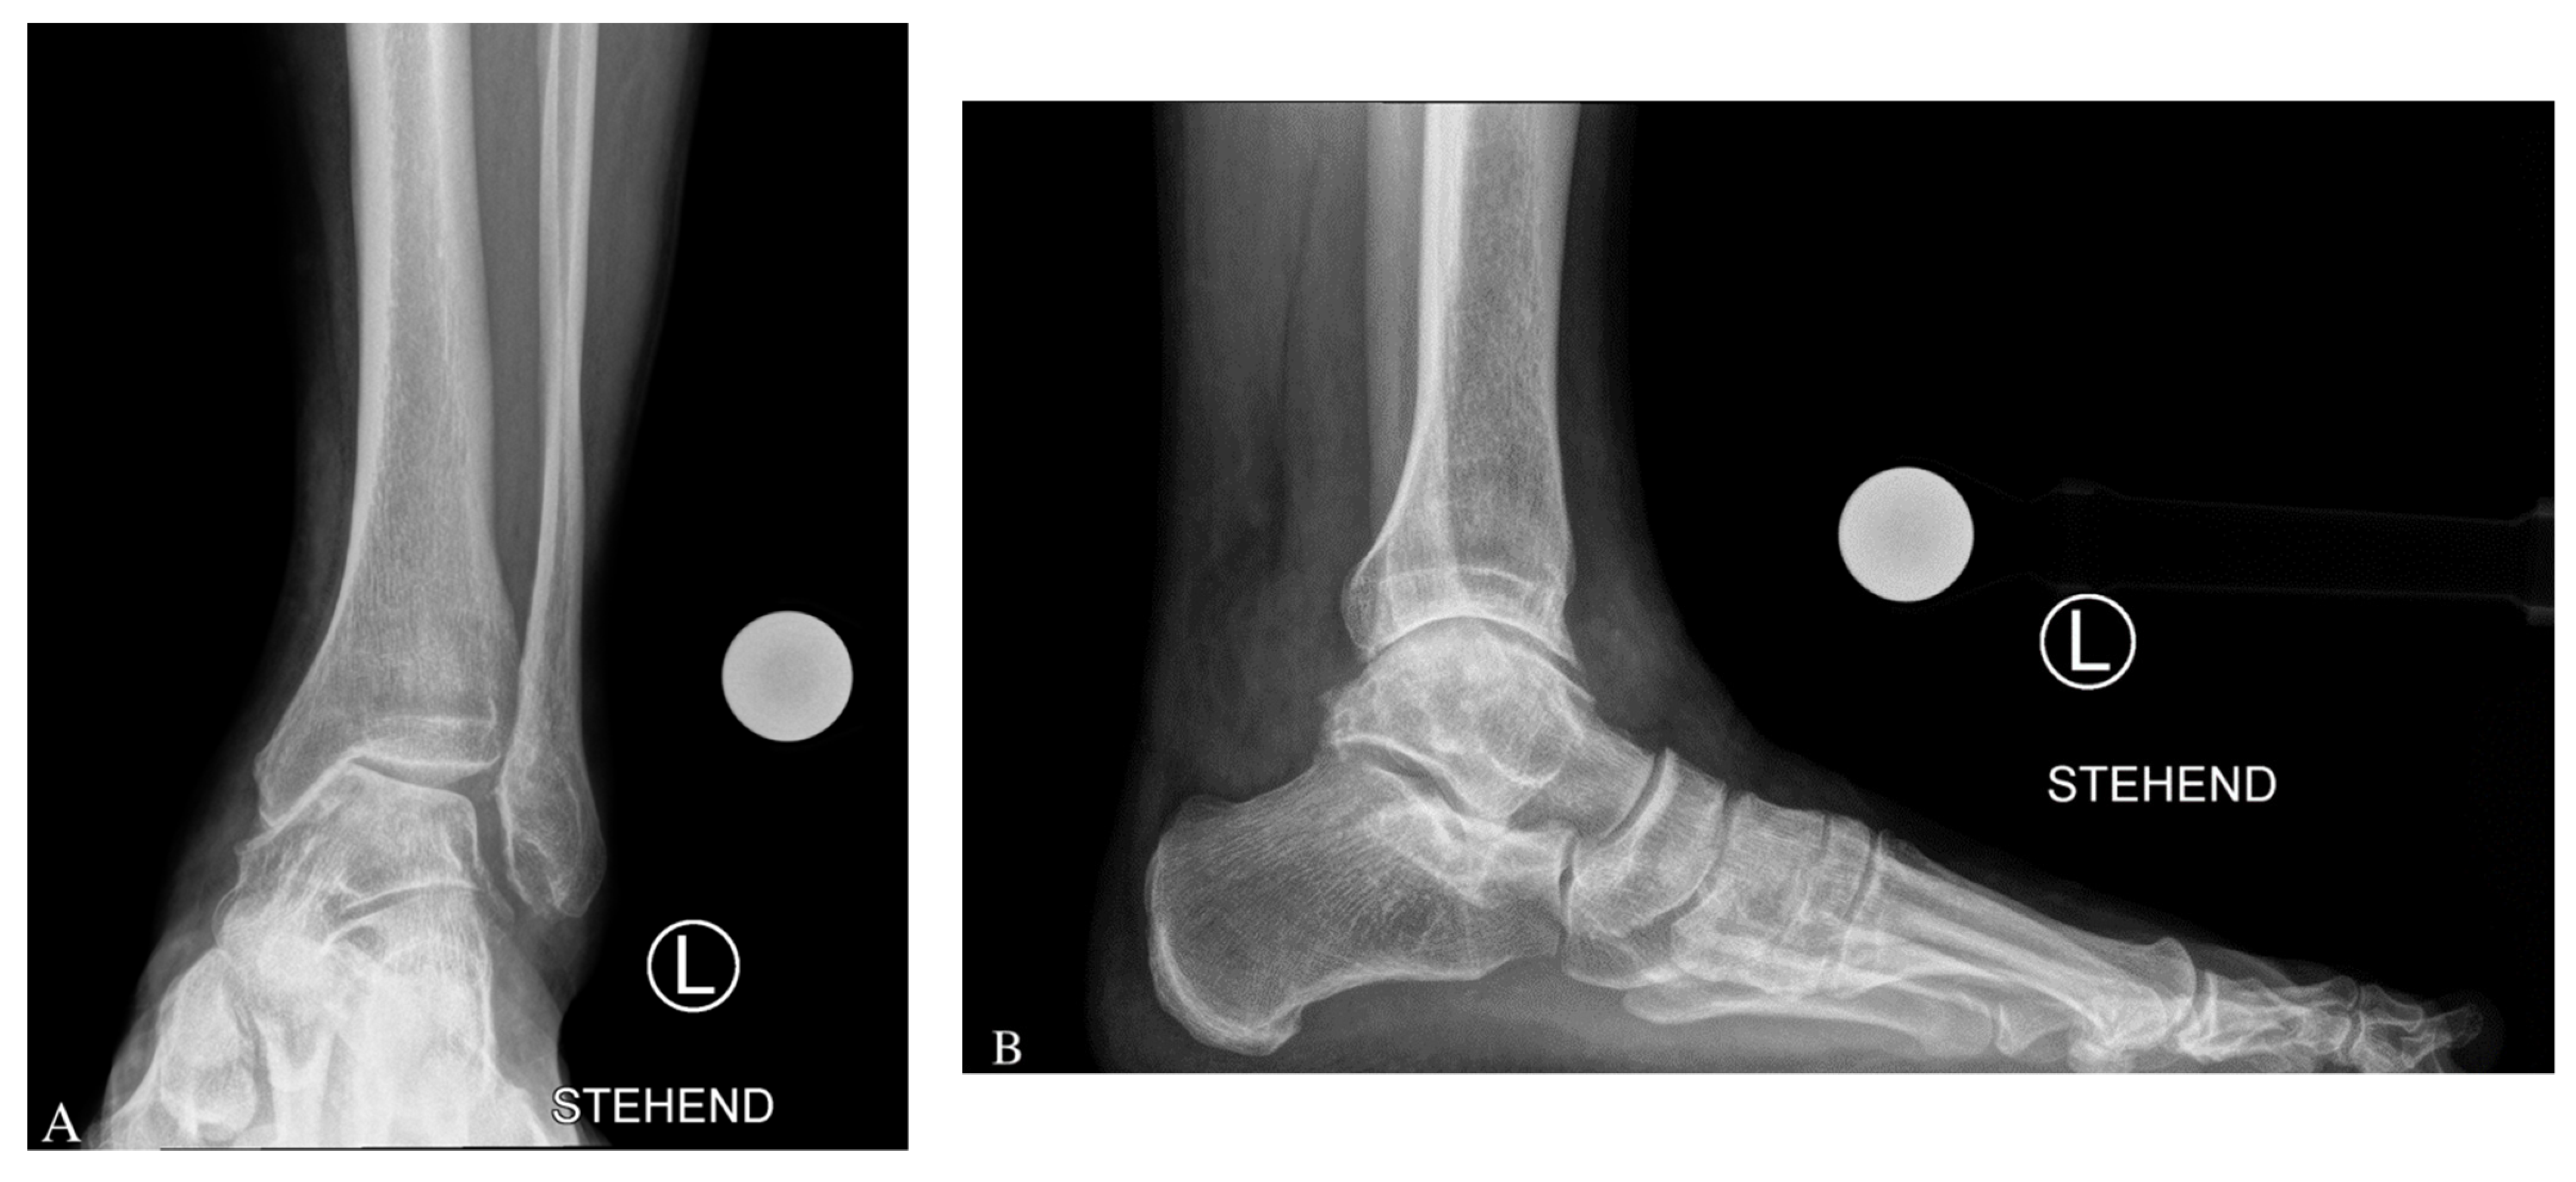

3.1. Imaging Modalities

3.2. Preoperative Radiological Angle Measurements